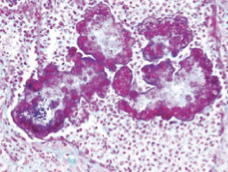

What bacteria causes greasy pig disease/ exudative epidermitis?

Staphylococcus hyicus subsp. hyicus

In what animals does greasy pig disease occur?

Mostly young (5-35 days)

High morbidity and mortality

What is the pathogenesis of greasy pig disease?

Bacteria secrete exfoliative toxins (Exh) which digest intercellular proteins between keratinocytes

How does greasy pig disease present grossly?

Accumulation of greasy brown exudate in multiple body locations (acute form) which then dried out, forming crusts with multifocal erythema (chronic)

How does greasy pig disease present histologically?

Hyperkeratosis (both ortho and para)

Neutrophilic pustules with intra-lesional bacteria

Neurtrophilic dermatitis

^bacteria can be seen (basophilici stippling)